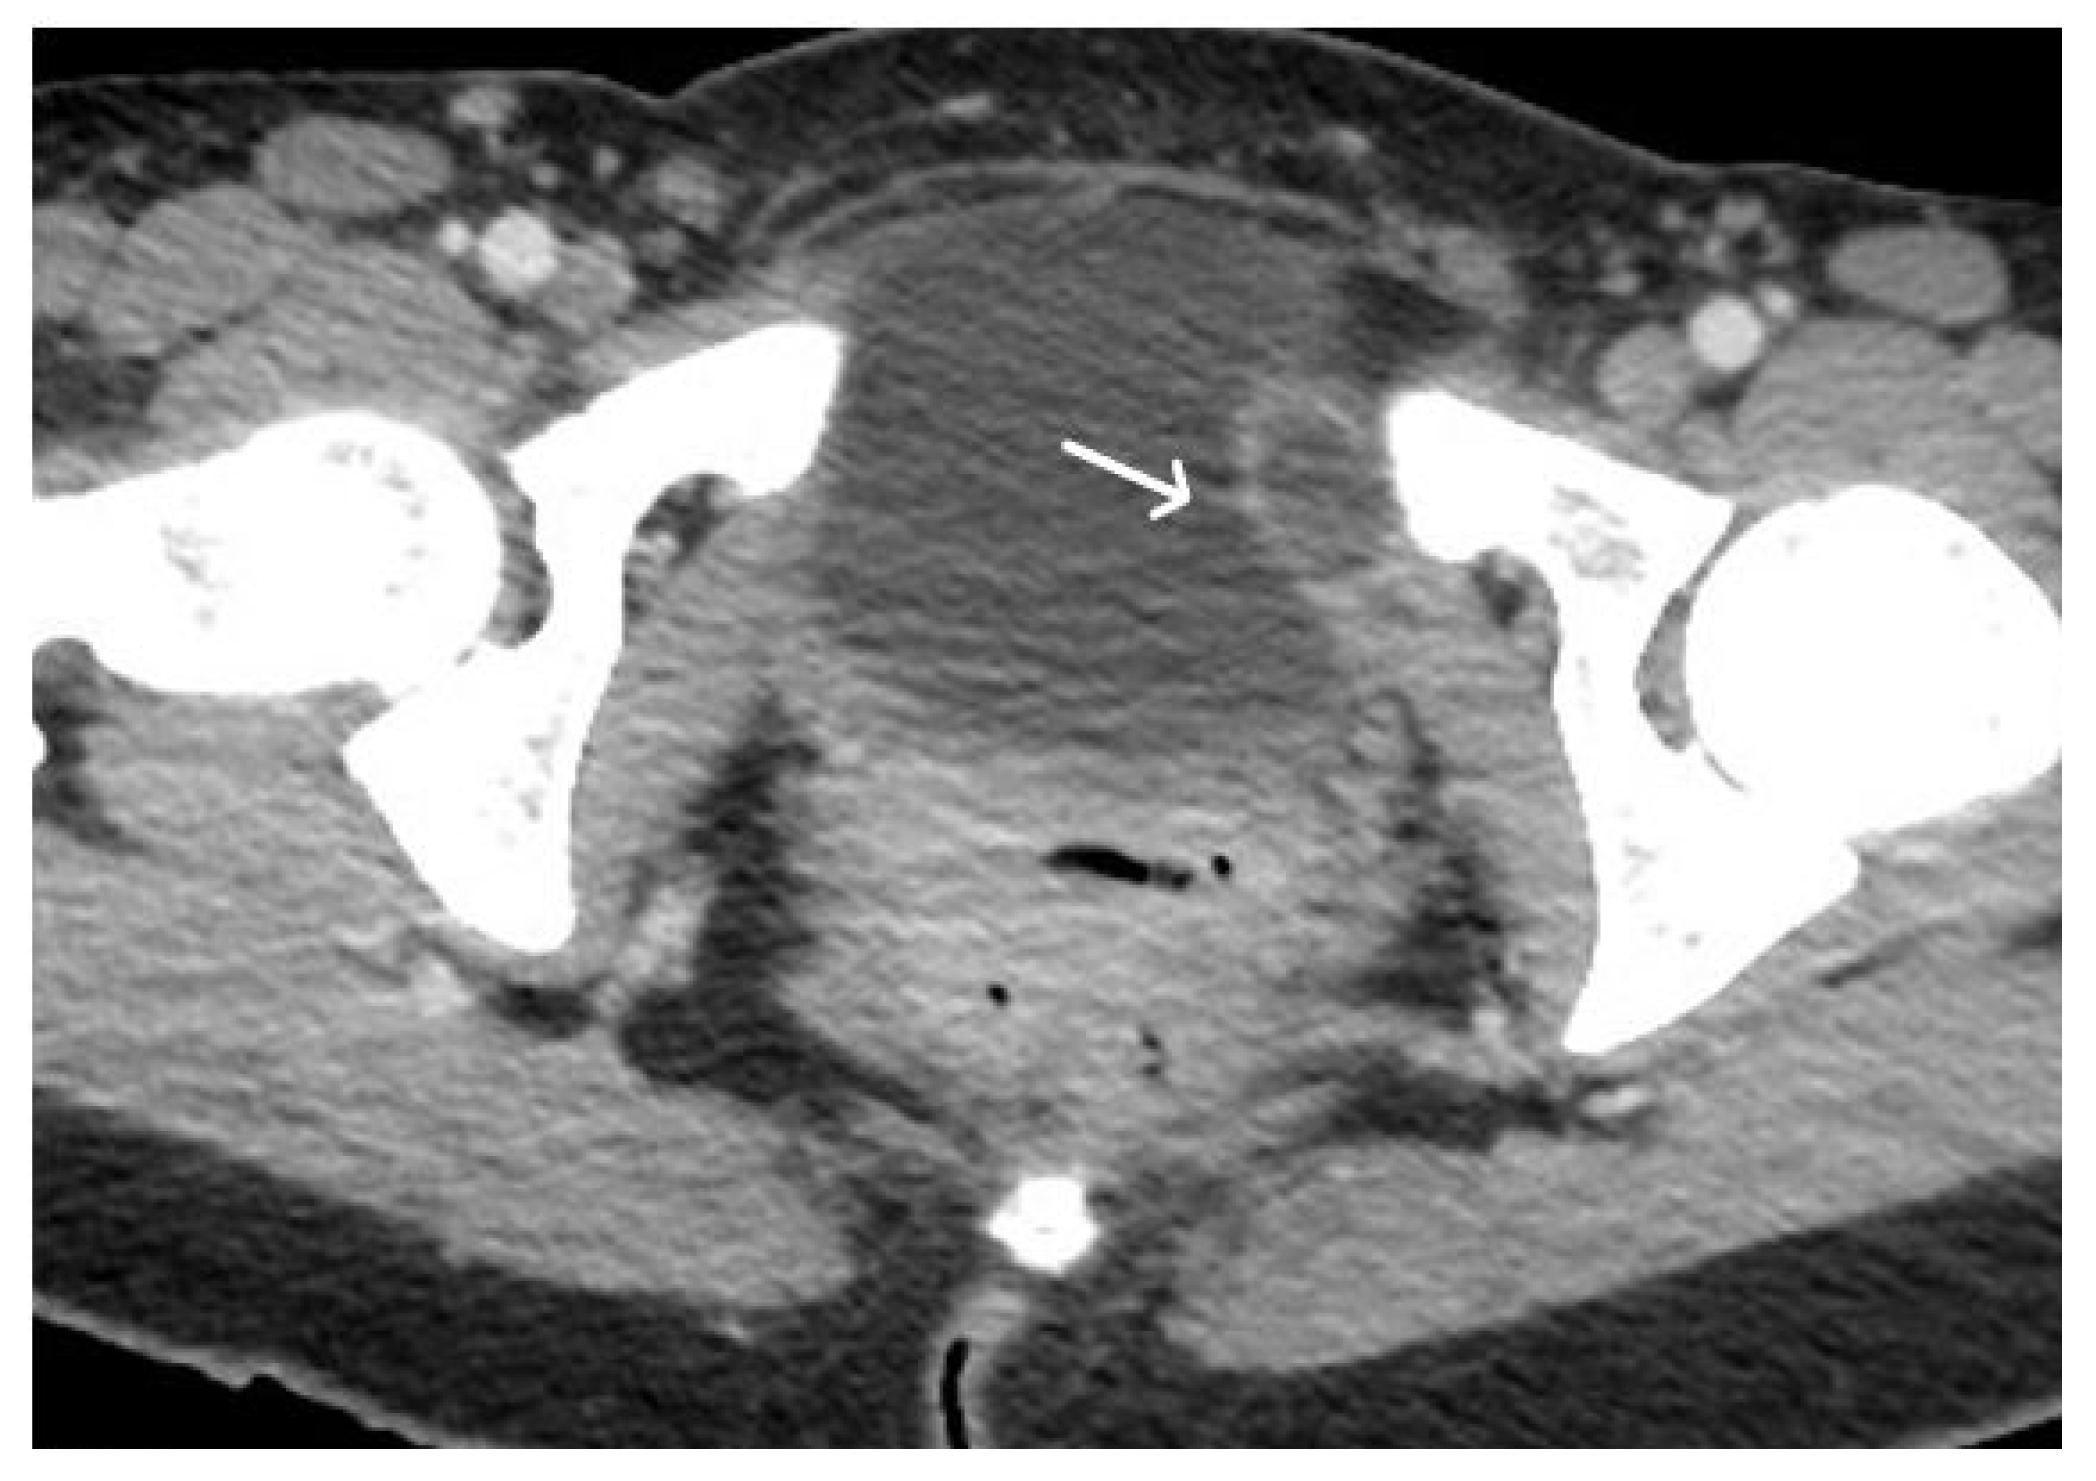

3. Normal Appearance of Urethral Meshes on MRI/CT

4. Urethral Mesh in Oncological Patients